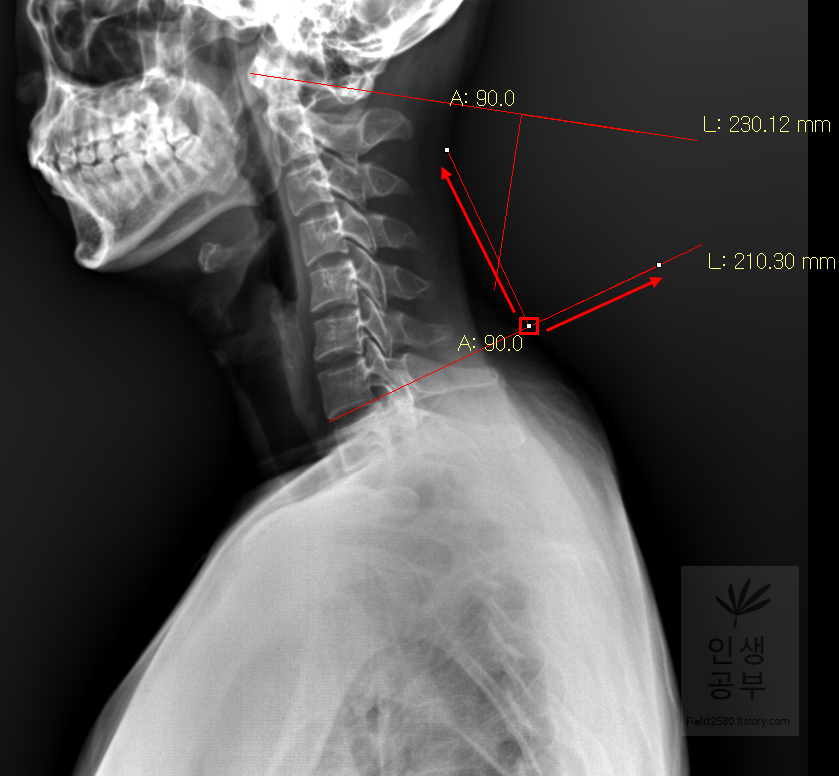

선 긋기를 이용해서 Cobb각을 그린다고 가정했을 때 측정하려고 하는 곳을 처음에 누르고 드래그로 쭉 끌어다주면 위와 같은 선이 생기고 선의 길이가 자동으로 측정됩니다. 첫 번째 목뼈(C1) 선을 그리기 위해 제일 튀어나온 앞쪽 부분 가운데 지점에(Center of Anterior arch) 점을 찍어줍니다. 후궁(Posterior arch) 제일 좁은 부위 가운데 지점에 점을 찍어줍니다. 두 점을 연결해주는 선을 그어줍니다. 이 선 이름을 고리 뼈 선(APL : Atlas Plane Line)이라고 합니다. 점은 조금 더 정확하기 위해서 하는 것이 찍어도 되고, 점을 찍지 않은 상태에서 선을 그으셔도 무방합니다.

일곱번째 목뼈 추체 밑면(Inferior endplate of C7)과 평행한 선을 그어줍니다.

두 선사이에 수직인 선을 그어야 하기 때문에 각도기 모양이 있는 버튼을 눌러줍니다.

위쪽 선을 따라서 선을 긋고 90도를 맞춰서 선을 그어줍니다. 동그라미 표시된 곳을 먼저 찍어주고, 화살표를 따라서 위쪽 선을 따라서 그려주고, 90도 방향에 맞춰서 아래로 그어줍니다. 노란색 글자와 숫자가 아래줄 맞춰 준 곳에 있는데 A는 Angle 각도이고 옆에 있는 숫자가 현재 긋고 있는 각도의 값입니다

아래 선을 따라서 선을 긋고 90도에 맞춰서 선을 그어줍니다. 동그라미 표시된 곳을 먼저 찍어주고, 화살표를 따라서 아래쪽 선을 따라서 그려주고 90도 방향에 맞춰서 위로 그어줍니다. 위쪽 선에서 그은 선과 교차되게 그어주시면 됩니다.

두 선이 교차된 곳에서 각도가 생기게 됩니다. 이 각도를 Cobb 각이라고 합니다. 위쪽에 각도를 재거나 아래쪽에 각도를 재어도 똑같으니 원하는 방향의 각도를 측정해 주시면 됩니다. 각도를 측정할 때에는 두선이 교차한 곳에 먼저 클릭해주고 위 화살표 방향대로 오른쪽 왼쪽의 교차한 선을 따라서 측정해 주시면 됩니다. 왼쪽선을 먼저 그어도 되고 오른쪽 선을 먼저 그어도 상관없습니다.

위쪽에 있는 선은 첫 번째 목뼈(C1) 선을 그리기 위해 제일 튀어나온 앞쪽 부분 가운데 지점에(Center of Anterior arch)에서 시작해서 후궁(Posterior arch) 제일 좁은 부위 가운데를 지나는 선이 되도록 이동해줍니다. 선 이름을 고리 뼈 선(APL : Atlas Plane Line)이라고 합니다. 점은 조금 더 정확하기 위해서 하는 것이 찍어도 되고, 점을 찍지 않은 상태에서 선을 그으셔도 무방합니다. 아래쪽에 있는 선은 일곱번째 목뼈 추체 밑면(Inferior endplate of C7)과 평행하게 선을 맞춰줍니다. 노란색 글자와 숫자가 아래줄 맞춰 준 곳에 있는데 A는 Angle 각도이고 옆에 있는 숫자가 Cobb 각입니다.